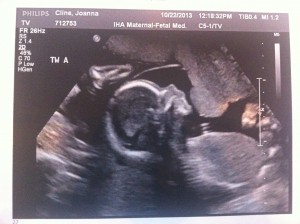

Hello! I had my bi-weekly ultrasound today and, if a triplet pregnancy appointment could be uneventful, this one was it!

Everything still looks great. The triplets are growing but we won’t have another growth scan until my 22wk appointment. Heart beats look good and it’s clear they’re getting bigger (Today’s pictures attached.)